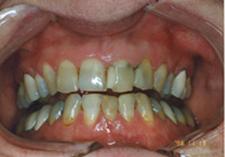

Parodontite moderate

dintii par alungiti datorita retractiei gingivale

pot apare abcese parodontale

halena

mobilitate dentara si diastemizare patologica

pungi parodontale de 4-6 mm

resorbtie osoasa

Parodontite severe

mobilitate dentara accentuata pâna la avulsia dintilor

migrari patologice

halena constanta

hiperestezie dentinara datorata denudarii radacinii

pungi parodontale > de 6 mm

resorbtie osoasa accentuata